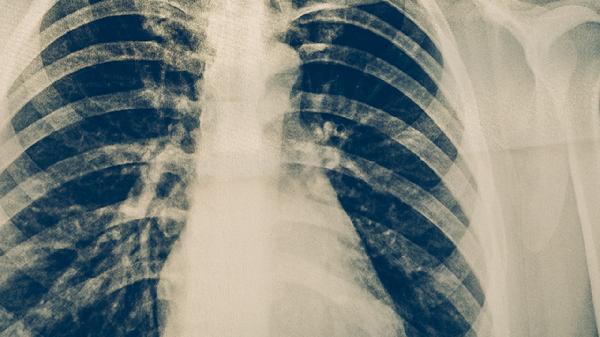

胸部CT检查比X线检查更敏感,能更清晰显示肺部病变细节,有助于发现早期微小病灶和评估病变范围。CT可显示肺结核特征性的树芽征、小叶中心结节等表现。对于痰涂片阴性但临床高度怀疑肺结核的患者,CT检查具有重要诊断价值。CT还可用于评估治疗效果和随访复查。